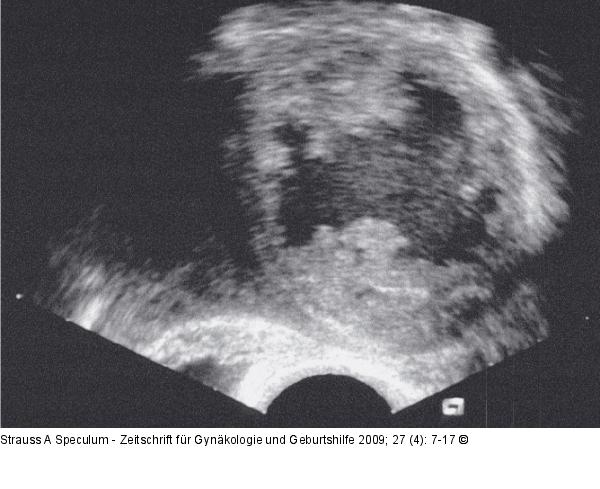

Abbildung 2a: Fundusmyom Kolliquationsnekrose: Transvagnialsonographische Darstellung des zentralen Zerfalls eines großen Fundusmyoms. |

Abbildung 2a: Fundusmyom

Kolliquationsnekrose: Transvagnialsonographische Darstellung des zentralen Zerfalls eines großen Fundusmyoms. |